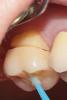

dr.moskvichev Опубликовано 17 августа, 2013 Поделиться Опубликовано 17 августа, 2013 После удаления композита и кариеса выбор пал на керамические вкладки. Временные реставрации изготовил из Protemp 4 по ключу из силикона, обработал дентин-герметизующим ликвидом, дебондинг,одномоментный двухслойный оттиск Express, временная цементировка на Temp NE. Техническая работа заняла неделю Времяшки выдержали, зубы не болели, незначительная гиперестезия к концу недели. Фиксировал на вариолинк 2. На следующий день после фиксации отмечалась слабовыраженная гиперестезия, которая исчезла на второй день. Основной вопрос: Будут ли такие конструкции состоятельные в отношении прочности(особенно при боковой нагрузке) в отдаленные результаты? Вопрос назрел в связи с большим межокклюзионным растоянием между буграми препарированных зубов и антагонистов (коронки м.к). Хватит ли силы адгезии для удержания таких крупных вкладок? Спасибо за внимание. 11 Ссылка на комментарий

ger_berra Опубликовано 17 августа, 2013 Поделиться Опубликовано 17 августа, 2013 ТС,чем Вы руководствовались,оставляя дентиновые рога,безбожно скосив эмаль? 1 Ссылка на комментарий

dr.moskvichev Опубликовано 17 августа, 2013 Автор Поделиться Опубликовано 17 августа, 2013 ТС,чем Вы руководствовались,оставляя дентиновые рога,безбожно скосив эмаль?Как раз-таки макромеханической ретенцией....Щечные бугры имеют прямой контакт с антагонистами, выводить их вестибулярнее было бы не правильно. Не хотел размещать границу препа в оклюзионных точках вот и все...Ведь здесь не классическая ортогнатия.. Классические полости "Бородатого" не учитывают отклонения в окклюзии. Уступ с вестибулярной стороны и рога именно для улучшения макромеханической ретенции а так же для увеличения площади адгезивной фиксации..... Ссылка на комментарий

ger_berra Опубликовано 17 августа, 2013 Поделиться Опубликовано 17 августа, 2013 Как раз-таки макромеханической ретенцией....Щечные бугры имеют прямой контакт с антагонистами, выводить их вестибулярнее было бы не правильно. Не хотел размещать границу препа в оклюзионных точках вот и все...Ведь здесь не классическая ортогнатия.. Классические полости "Бородатого" не учитывают отклонения в окклюзии. Уступ с вестибулярной стороны и рога именно для улучшения макромеханической ретенции а так же для увеличения площади адгезивной фиксации.....Меня интересуют "дентиновые кружева".Почему не сделали классический оверлей?Почему скосили столько эмали вестибулярно,оставив "рога"? Ссылка на комментарий